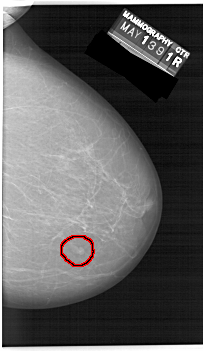

A_1471_1.LEFT_MLO

LEFT_MLO LINES 6871 PIXELS_PER_LINE 4036 BITS_PER_PIXEL 12 RESOLUTION 43.5 NON_OVERLAY

FILE: A_1471_1.RIGHT_MLO.OVERLAY

TOTAL_ABNORMALITIES 1

ABNORMALITY 1

LESION_TYPE MASS SHAPE LOBULATED MARGINS CIRCUMSCRIBED

ASSESSMENT 4

SUBTLETY 4

PATHOLOGY BENIGN

TOTAL_OUTLINES 1

BOUNDARY